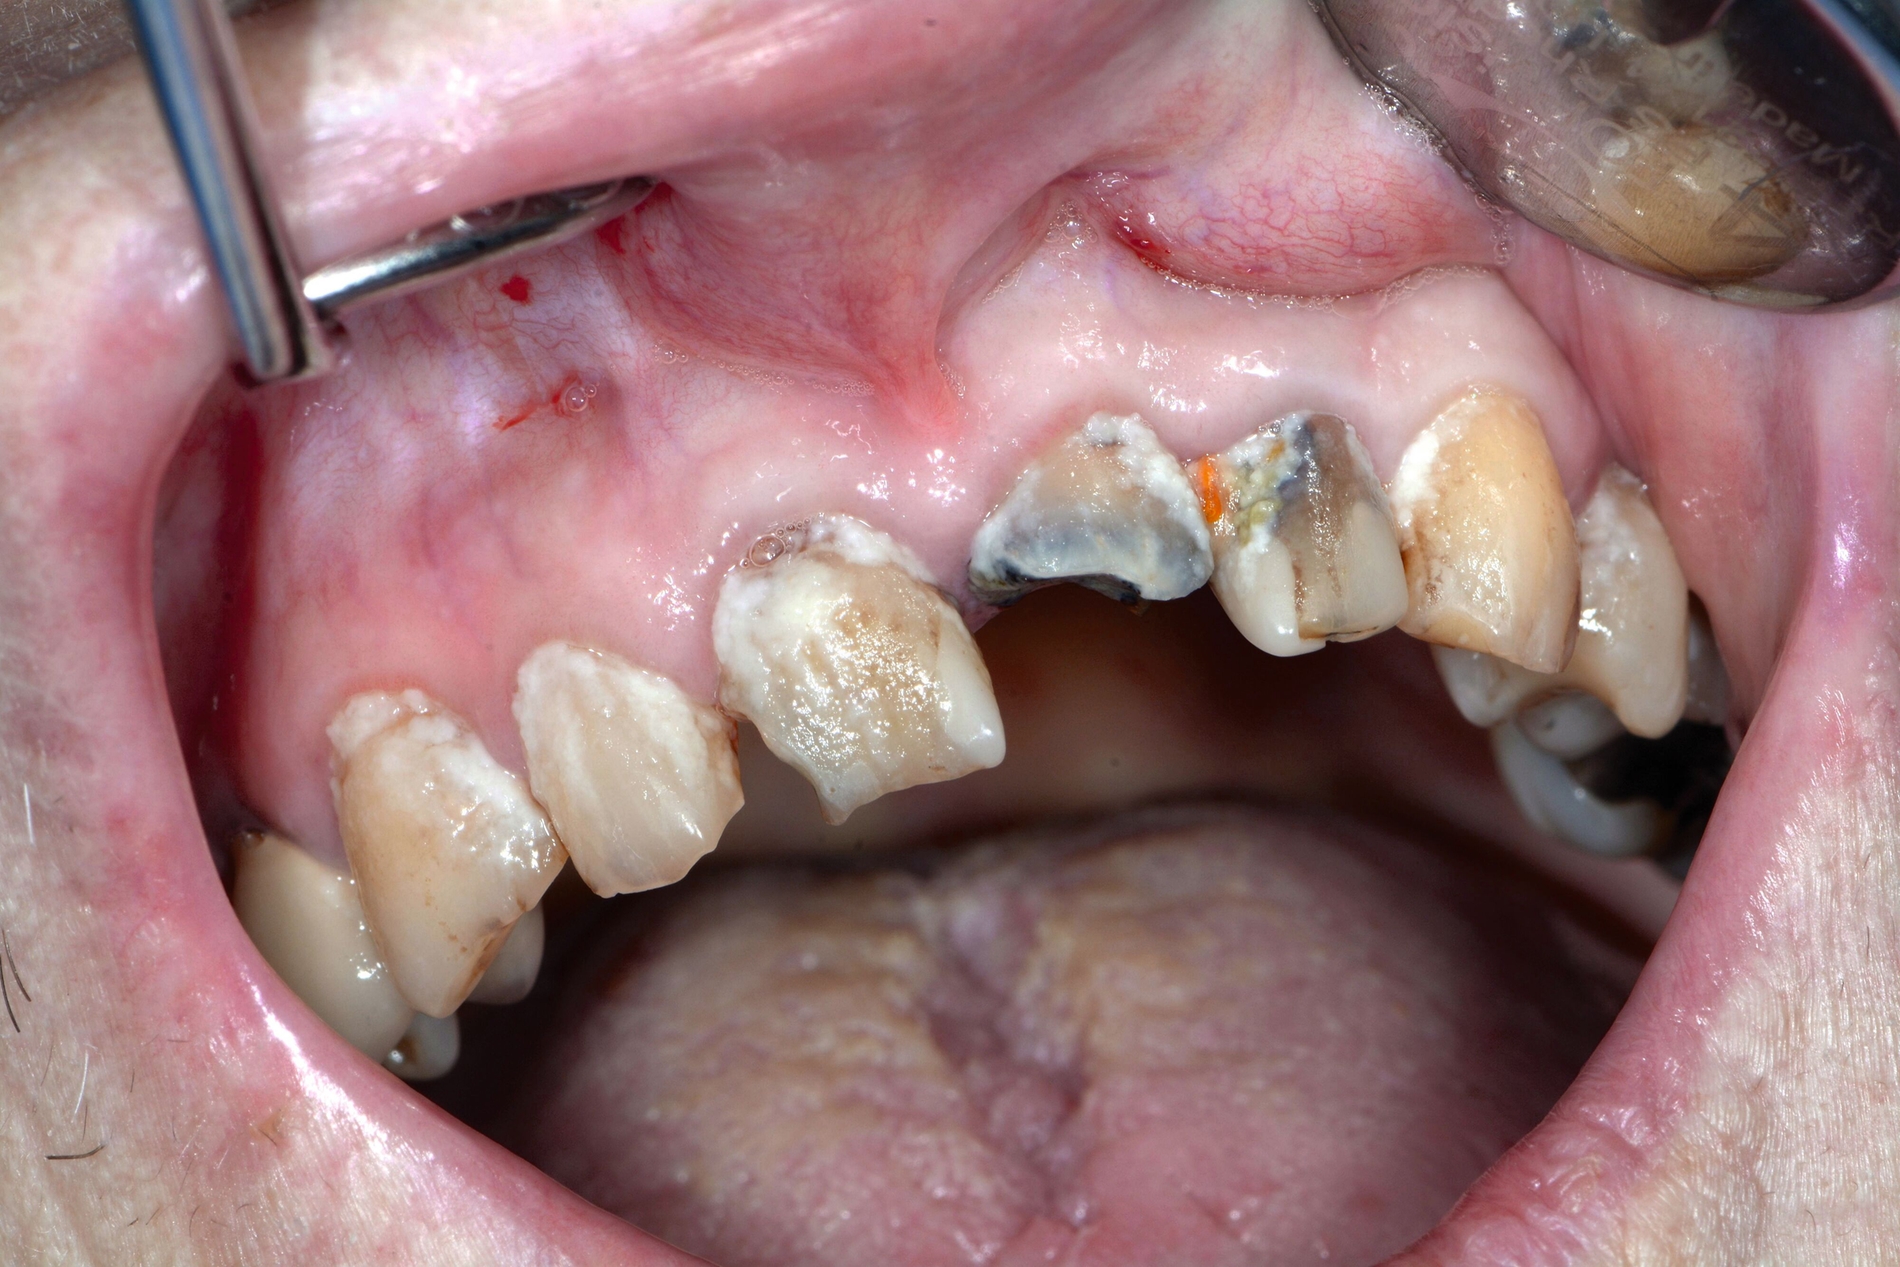

Zahnmedizinische Leitlinien zur zahnmedizinischen Betreuung von geriatrischen und demenziell erkrankten PatientInnen sind aktuell im Entstehungsprozess. Zusätzlich zu den oft komplexen zahnmedizinischen Befunden müssen bei der individuellen Therapieplanung dieser vulnerablen Klientel die Therapiefähigkeit und die Eigenverantwortlichkeit berücksichtigt werden. Dabei ist es weniger das Alter, sondern vielmehr der Zustand der körperlichen und mentalen Funktionsfähigkeit, der den Erfolg zahnmedizinischer Therapien limitiert. Therapien, die bei gesunden Personen jahrelang das Alltagsgeschäft der Zahnmedizin waren, sind bei Personen mit erhöhtem Pflege- und/oder Unterstützungsbedarf eventuell nicht umsetzbar. Gebrechlichkeit (Frailty) ist ein Zustand zwischen guter Gesundheit und Pflegebedürftigkeit im Alter – ein Zwischenstadium, in dem ein vorher fitter älterer Mensch Symptome der Gebrechlichkeit entwickelt und die Gefahr besteht, dass sich sein Zustand verschlechtert. Die geriatrischen Erkrankungen Frailty und auch Demenz sind im Rahmen zahnmedizinischer Behandlungen mit einer reduzierten Kooperations- und Therapiefähigkeit sowie bei der Anfertigung von Zahnersatz mit einer reduzierten Adaptationsfähigkeit assoziiert (Abbildung 3).

Auch wenn sich Karies, Parodontitis und dentale Traumata bei dieser vulnerablen Hochrisikogruppe in absehbarer Zeit wohl nicht gänzlich vermeiden lassen, ermöglicht die regelmäßige zahnmedizinische Kontrolluntersuchung, dass einzelne Befunde frühzeitig identifiziert und mit moderatem Aufwand therapiert werden können (Abbildung 5). Bei stark reduzierter Therapiefähigkeit sollten als Minimalziel die oralen Strukturen schmerz- und entzündungsfrei sein, um lebensbedrohliche Komplikationen wie Pneumonien oder Bakteriämien zu verhindern. Parodontale und periimplantäre Erkrankungen sollten im Kontext des allgemeinen Gesundheitszustands, der physiologischen Alterung des Immunsystems und der allgemeinen Körperfunktion beurteilt werden [Paris et al., 2020; Müller et al., 2022]. Prothetische Rehabilitationen sind zum Erhalt der Kaufunktion und der mundgesundheitsbezogenen Lebensqualität je nach Lokalisation und Ausmaß des Zahnverlusts sinnvoll, bedingen aber ein Mindestmaß an Mitarbeit von Patient und betreuendem Umfeld. Eine möglicherweise reduzierte Adaptationsfähigkeit an neu angefertigten Zahnersatz gilt es besonders bei neurodegenerativen Erkrankungen im Vorfeld der Therapie zu besprechen [Nitschke et al., 2021].

Patientinnen und Patienten mit stark reduzierter Therapiefähigkeit profitieren in besonderem Maß von zeiteffektiven Methoden und Materialien, zum Beispiel Bulk-fill-Kompositen, Reparaturfüllungen, Glasionomerzementen oder Intraoralscans. Die Therapiefähigkeit kann – ähnlich wie in der Kinderzahnmedizin – durch ein vertrauensvolles Verhältnis optimiert werden. Anders als in der Kinderzahnmedizin gibt es in der Alterszahnmedizin aber keine altersassoziierten Kontraindikationen für zahnmedizinische Interventionen. Voraussagbare Therapieergebnisse sind von besonderer Bedeutung, um erneute Behandlungen zu vermeiden. Das gesamte Spektrum zahnmedizinischer Interventionen kann bei der Behandlung von Personen mit Pflegebedarf sinnvoll sein. Die Abbildungen 6 bis 9 zeigen zahnmedizinische Interventionen bei Personen mit ausgeprägter Frailty (Stufe 7 der klinischen Frailty-Skala).